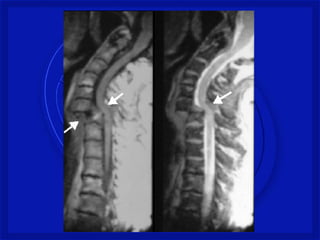

• Lesão medular cervical é a mais comum – 2/3

• C4 a C7 – mais vulnerável a lesão

• Torácica - proteção de costelas

• Toracolombar – T11, T12 e L1

• Lesão estável ou instável

Gravidade do trauma • DEPENDE SE A MEDULA É ATINGIDA • Lesão medular cervical é a mais comum – 2/3 • C4 a C7 – mais vulnerável a lesão • Torácica - proteção de costelas • Toracolombar – T11, T12 e L1 • Lesão estável ou instável • Difícil de avaliar no pré hospitalar. • Considerar toda lesão instável até se prove o contrario